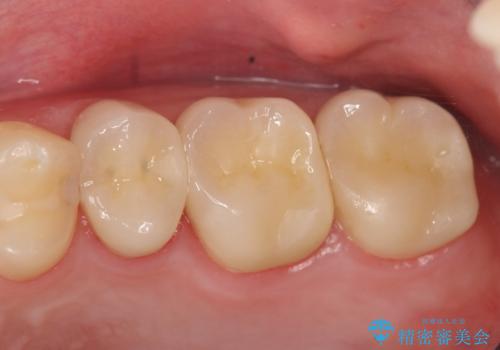

オールセラミッククラウンについて

今回用いたオールセラミッククラウンはジルコニアフレームという白い素材の上にセラミックを盛っているため、審美性が非常に高いのが特徴です。

また、ジルコニアは人工ダイヤモンドの材料にも使われているほど高い強度を持っており、そのためオールセラミッククラウンは審美性だけでなく、奥歯やブリッジの補綴も可能とするクラウンです。